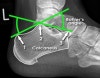

X-ray : Normal calcaneus(Lateral view)

X-ray : 종골 골절(Calcaneal fracture) - Lateral view

1. Flattening of Bohler's angle

2. Depression of the articular surface of the posterior subtalar joint (red line)

from its normal position (green line)

3. Fracture lines can be seen passing through the calcaneus